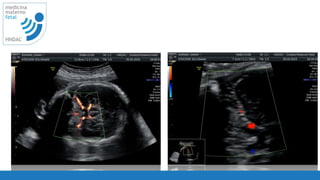

movimientos

respiratorios

22